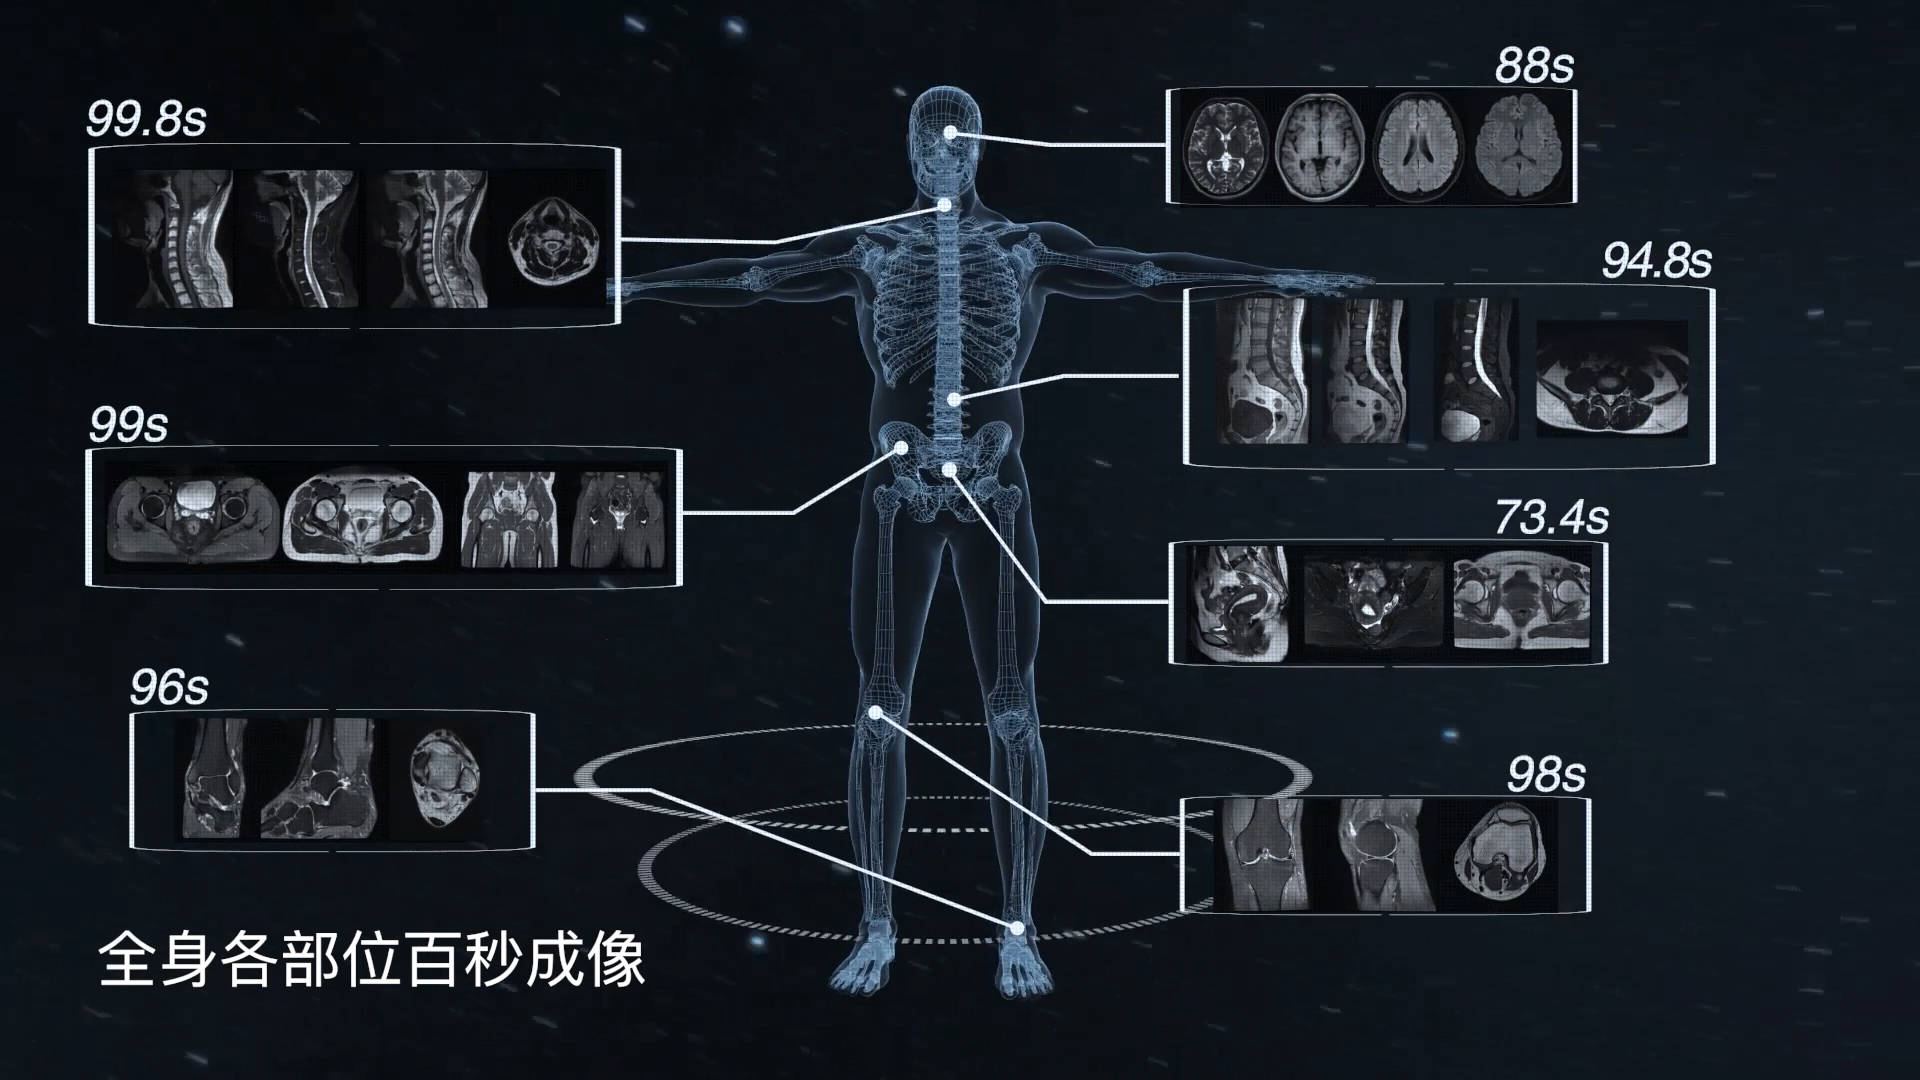

核磁共振下的人体运动

图片尺寸1920x1080